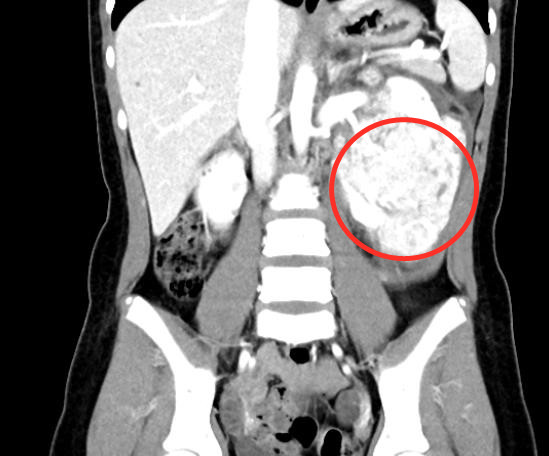

CT显示:左肾有一个巨大肿瘤(红圈内)。

2020年35日凌晨时分,小丽突然出现剧烈腹痛,家长开始还以为是痛经,谁知疼痛持续加剧,还出现2次呕吐,家长赶紧驱车将女儿送往当地捷克论坛 看急诊。CT结果显示,小丽的左侧腹腔内有一个柚子大小的肿块,右肾和肝脏内也有囊性病变。父母当天便带着女儿赶往长沙,来到有“三湘第一儿科”之称的捷克论坛 儿童医学中心就诊。

该院儿童血液肿瘤科主任贺湘玲教授和儿七科主任张先华教授等为小丽进行检查发现,其左上腹的巨大包块质地较硬,边界不清,腹部增强CTCTA检查显示“左肾巨大肿瘤并破裂出血、右肾多发囊肿、多发性肝囊肿、右肺多发小结节、结节性硬化”,需尽快手术治疗,于是将她转入泌尿三科病房。

郭玺副主任医师结合小丽的病史和检查结果,初步考虑为“结节性硬化症”累及肾脏导致“双侧多发肾血管平滑肌脂肪瘤”。此疾病治疗的总体原则是最大限度保留肾脏功能,延长患者生存时间,减少肿瘤破裂出血的发生。但小丽的左肾肿瘤已经破裂出血且体积巨大,郭玺坦言,如果只进行左肾及肿瘤切除的话,难度并不大;但要完整切除包裹肾门血管的巨大多发肿瘤同时保住左肾的话,面临的风险与挑战极大。

经过5个多小时紧张有序的精准解剖后,“王炸”医生团队完整切除小丽左肾巨大肿瘤,并妥善处理好被肿瘤包裹的肾动静脉及各级分支。切下的肿瘤约16×12×5cm3,重达1.5kg,术中出血仅50ml,术后肾功能正常。